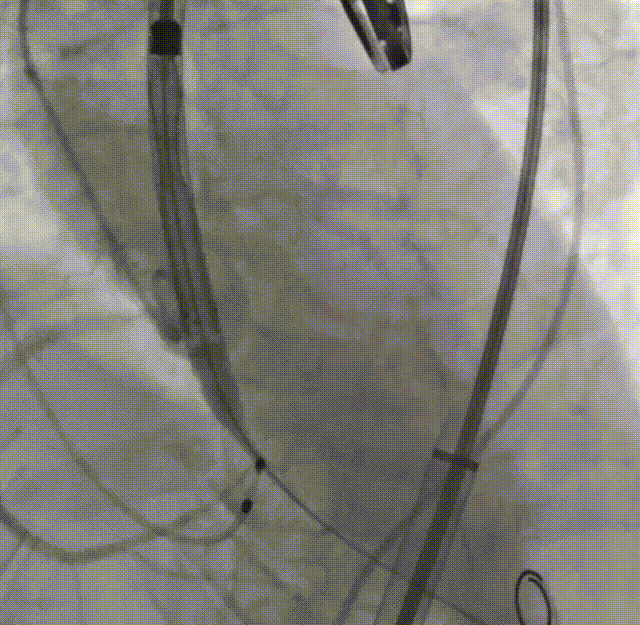

整体入路造影,右侧细,走左侧为主入路,左侧用外周球囊预扩后送大鞘

20mm球囊预扩,球囊下滑

再次预扩,球囊上跳

瓣下3mm定位

释放到工作位,瓣下5mm左右

缓慢脱钩

左冠窦侧微量反流

22mm球囊后扩